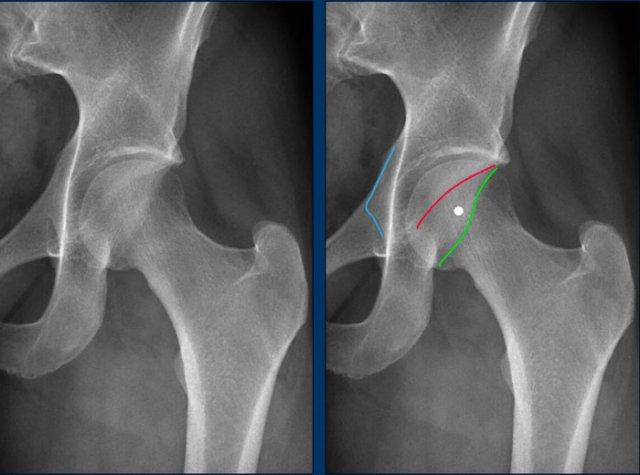

Alpha angle measurement

Hông bình thường có góc alpha nhỏ hơn 60º.

Hông có hình thái Cam có góc alpha lớn hơn 60º.

Tất nhiên, khi hình thái Cam rõ ràng như trong trường hợp này, các

phép đo này là không cần thiết trong thực hành lâm sàng.

Đây là một trường hợp hình thái Cam khá tinh tế ở một nam giới trẻ tuổi.

Lưu ý rằng sụn tăng trưởng mào chậu chưa đóng lại (mũi tên).

Images

Two examples of Cam morphology.